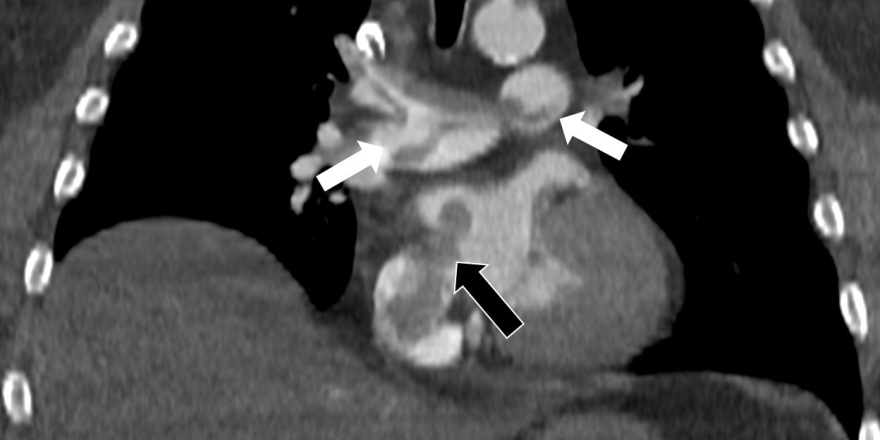

Kalp ve akciğer görüntülemesi alanındaki uluslararası bilimsel çalışmalarıyla tanınan Radyoloji Uzmanı Prof. Dr. Nevzat Karabulut, dünyanın önde gelen tıp dergilerinden Radiology dergisinin 2025 Kasım sayısında yayımlanan "Paradoxical Embolism with Clot-in-Transit in Atrial Septal Defect" adlı çalışmasında, penis ameliyatından 5 gün sonra ani göğüs ağrısı, nefes darlığı ve kol uyuşması şikâyetiyle hastaneye başvuran 60 yaşındaki bir hastada, daha önce fark edilmemiş kalp odacıkları arasındaki bir delikten geçen pıhtının hayati tehlike oluşturduğunu ortaya koydu.

Bir dönem Özel Denizli Tekden Hastanesi'nde de görev yapan Prof. Dr. Nevzat Karabulut'un yaptığı çalışmada; akciğerin bilgisayarlı tomografi anjiyografisi sayesinde toplar damarlardan kaynaklanan pıhtının akciğer damarlarını tıkaması yanında, kalpteki delik nedeniyle kalbin sağ tarafından sol tarafına geçerek ana atardamara ulaştığı ve sol kol damarını tıkadığı gösterildi.

Emboli görüntülemesi konusunda çok sayıda bilimsel çalışması bulunan Prof. Dr. Karabulut, genelde bacak damarlarından kaynaklanan pıhtıların ölümcül olabilen akciğer embolisine yol açması yanında, kalp deliği olan hastalarda ana atardamar yoluyla beyin, kol ve bacak gibi vücudun diğer bölgelerine de geçerek ani damar tıkanmasına (paradoks emboli) bağlı bulgulara yol açtığını belirtti. Prof. Dr. Karabulut'un çalışmasında nedeni bilinmeyen pıhtı atmalarında kalpteki gizli deliklerin mutlaka araştırılması gerektiği vurgulanarak ekokardiyografi ve bilgisayarlı tomografi tetkiklerinin erken ve doğru tanı koymada hayat kurtarıcı rolüne dikkat çekildi.